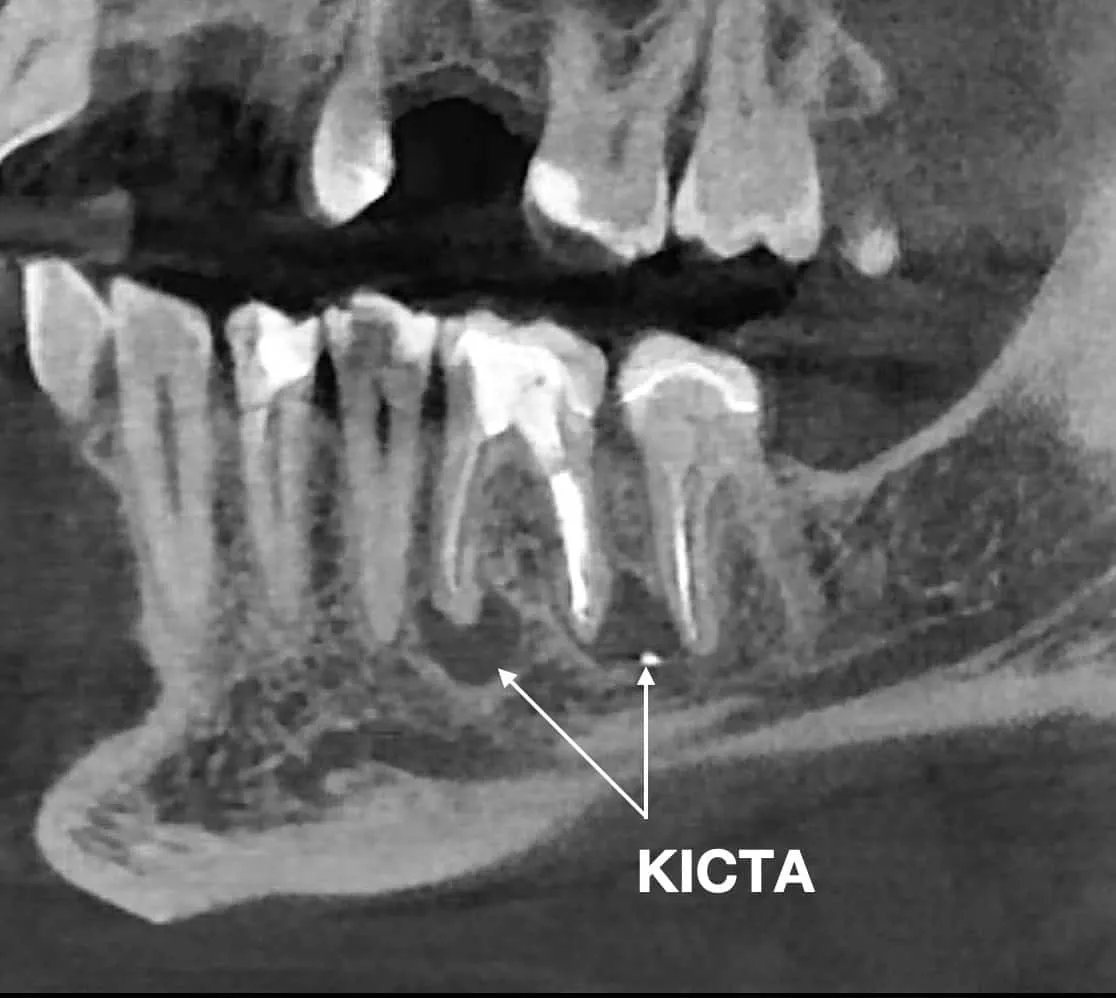

ПРИКЛАД УСПІШНОГО ВИДАЛЕННЯ КІСТИ ЗУБА В СТОМАТОЛОГІЧНОМУ ЦЕНТРІ OLANKO DENTAL STUDIO

Апікальна(ендодонтична) мікрохірургія - це зубозберігаюча операція, яка проводиться в ділянці верхівки кореня зуба, за допомогою хірургічного доступу через кістку, при цьому видалється інфікована частина кореня і зуб герметично пломбується ретроградно, через хірургічну рану. Вся операція проходить з використанням дентального мікроскопу і біосумісних матеріалів.

Показами до данної операциї являються ті клінічні випадки, при яких стандартне ендодонтичне лікування кореневих каналів не далопозитивного результату далопозитивного результату або в зубі є блоки, які не дають, якісно обробити кореневий такі як сходинки, зламані інструменти, атипова анатомія.

Також показами є істинні кісти та інфекція поза кореневим каналом на які ми не можемо вплинути через консервативне ендодонтичне лікування.

Часто апікальна хірургія є єдиним способом уникнути видалення зуба.